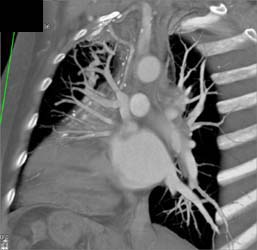

Patent Bypass Graft